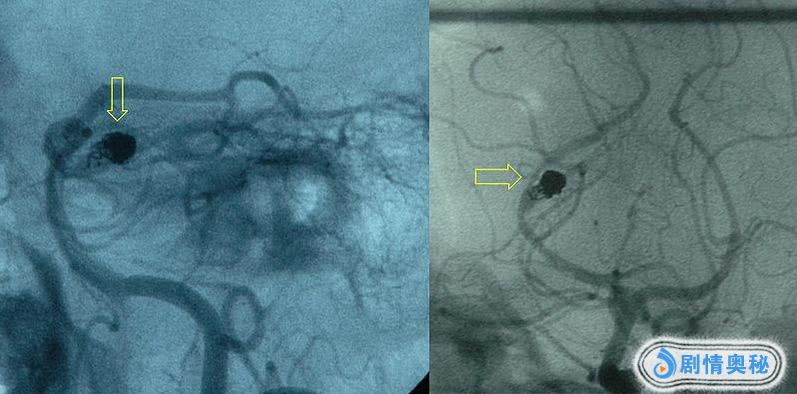

蛛网膜下腔出血。

医学影像:蛛网膜下腔出血

换言之,是大脑周围出血,导致的中风。

克拉克突发此症,便是因为她的脑部,有动脉瘤。

为了保护克拉克的形象,第一次采用微创手术。

手术需从大腿内侧的股动脉插入一根金属导管,经过克拉克自己的血液循环,流经心脏,到达大脑,随后展开手术。

资料图:动脉瘤微创手术示意

可是,第二次微创手术失败了。

事不宜迟,大夫决定对克拉克进行开颅手术。

资料图:开颅手术需剔除头发,切开头皮和头骨